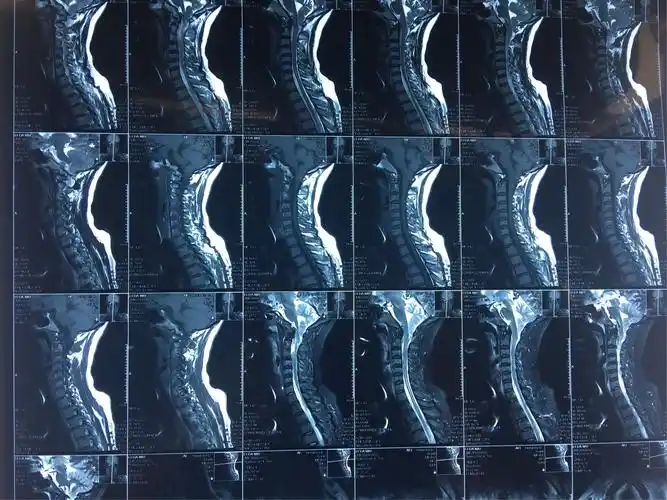

颈椎间盘突出成这样也可以不手术

颈椎间盘突出手术摘除 融合 固定.患者为45岁 - 抖音

颈椎间盘突出_颈椎间盘突出治疗方式 - 好大夫在线

入院后查颈椎mri示:椎间盘膨出,约平颈6以下颈胸髓内异常,考虑中央导